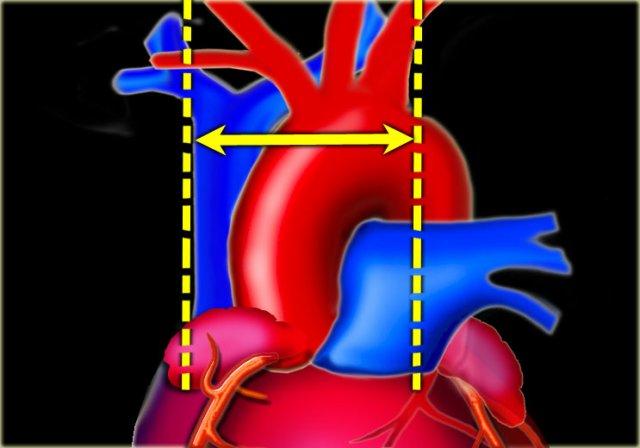

Chỉ số tim-ngực

Chỉ số tim-ngực (CTR) là tỷ lệ giữa đường kính ngang của tim so với đường kính trong của lồng ngực tại điểm rộng nhất ngay phía trên vòm hoành, được đo trên phim X-quang ngực tư thế thẳng (PA).

Bóng tim to hầu như luôn là hệ quả của tim to (cardiomegaly), nhưng đôi khi có thể do tràn dịch màng ngoài tim hoặc thậm chí do lắng đọng mỡ.

Kích thước tim được xem là quá lớn khi CTR > 50% trên phim X-quang ngực tư thế PA.

CTR > 50% có độ nhạy 50% và độ đặc hiệu 75-80% trong chẩn đoán suy tim sung huyết (CHF).

Thể tích thất trái cần tăng ít nhất 66% mới có thể nhận thấy được trên phim X-quang ngực.

Cuống mạch máu

Cuống mạch máu được giới hạn bên phải bởi tĩnh mạch chủ trên và bên trái bởi nguyên ủy của động mạch dưới đòn trái (6).

Cuống mạch máu là chỉ số phản ánh thể tích nội mạch.

Chiều rộng cuống mạch máu dưới 60 mm trên phim X-quang ngực tư thế PA được ghi nhận trong 90% trường hợp X-quang ngực bình thường.

Chiều rộng cuống mạch máu trên 85 mm có tính chất bệnh lý trong 80% trường hợp.

Mỗi 5 mm tăng thêm về đường kính tương ứng với 1 lít tăng thêm về dịch nội mạch.

Sự gia tăng chiều rộng cuống mạch máu thường đi kèm với sự gia tăng chiều rộng của tĩnh mạch đơn.